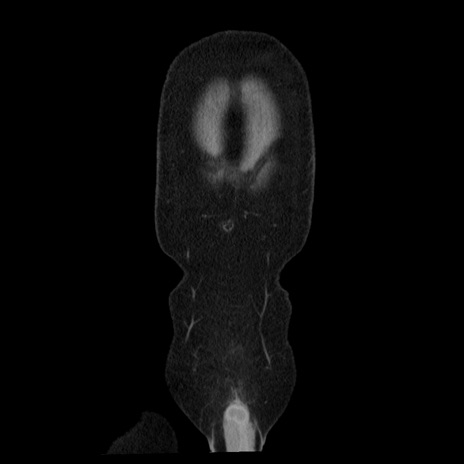

【症例】40歳代男性

【現病歴】2日前から胃痛あり。徐々に周期的な激痛に変化した。本日になっても激痛があるため受診。

【身体所見】意識清明、BT 38-39℃台あり、腹部:膨満、やや硬、右下腹部に圧痛あり。

【データ】WBC 8500、CRP 23.26